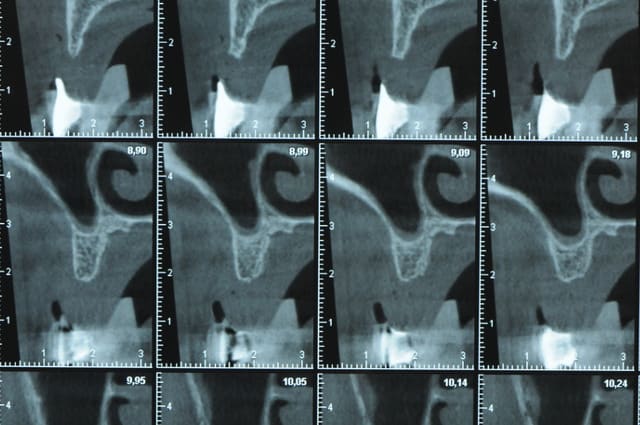

Une petite étude de ton cas D57

Les zones exploitables radiologiquement parlant:

Coupes implant

2,3 40100

4,96 35130 avec sinus lift mais difficile

5,25 35150

6,02 35130

6,78 35115 après réduction de hauteur de crête

7,26 35115 après réduction de hauteur de crête

8,51 35150

10,43 40115 ou 50115

11,10 40115

Ce qui nous fait 9 implants possible évidement avec un comblement de sinus on augmenterait encore les zones implantable mais ce n’est pas le but recherché, avec 8 (4+4) il doit être possible de faire une belle barre support de complet